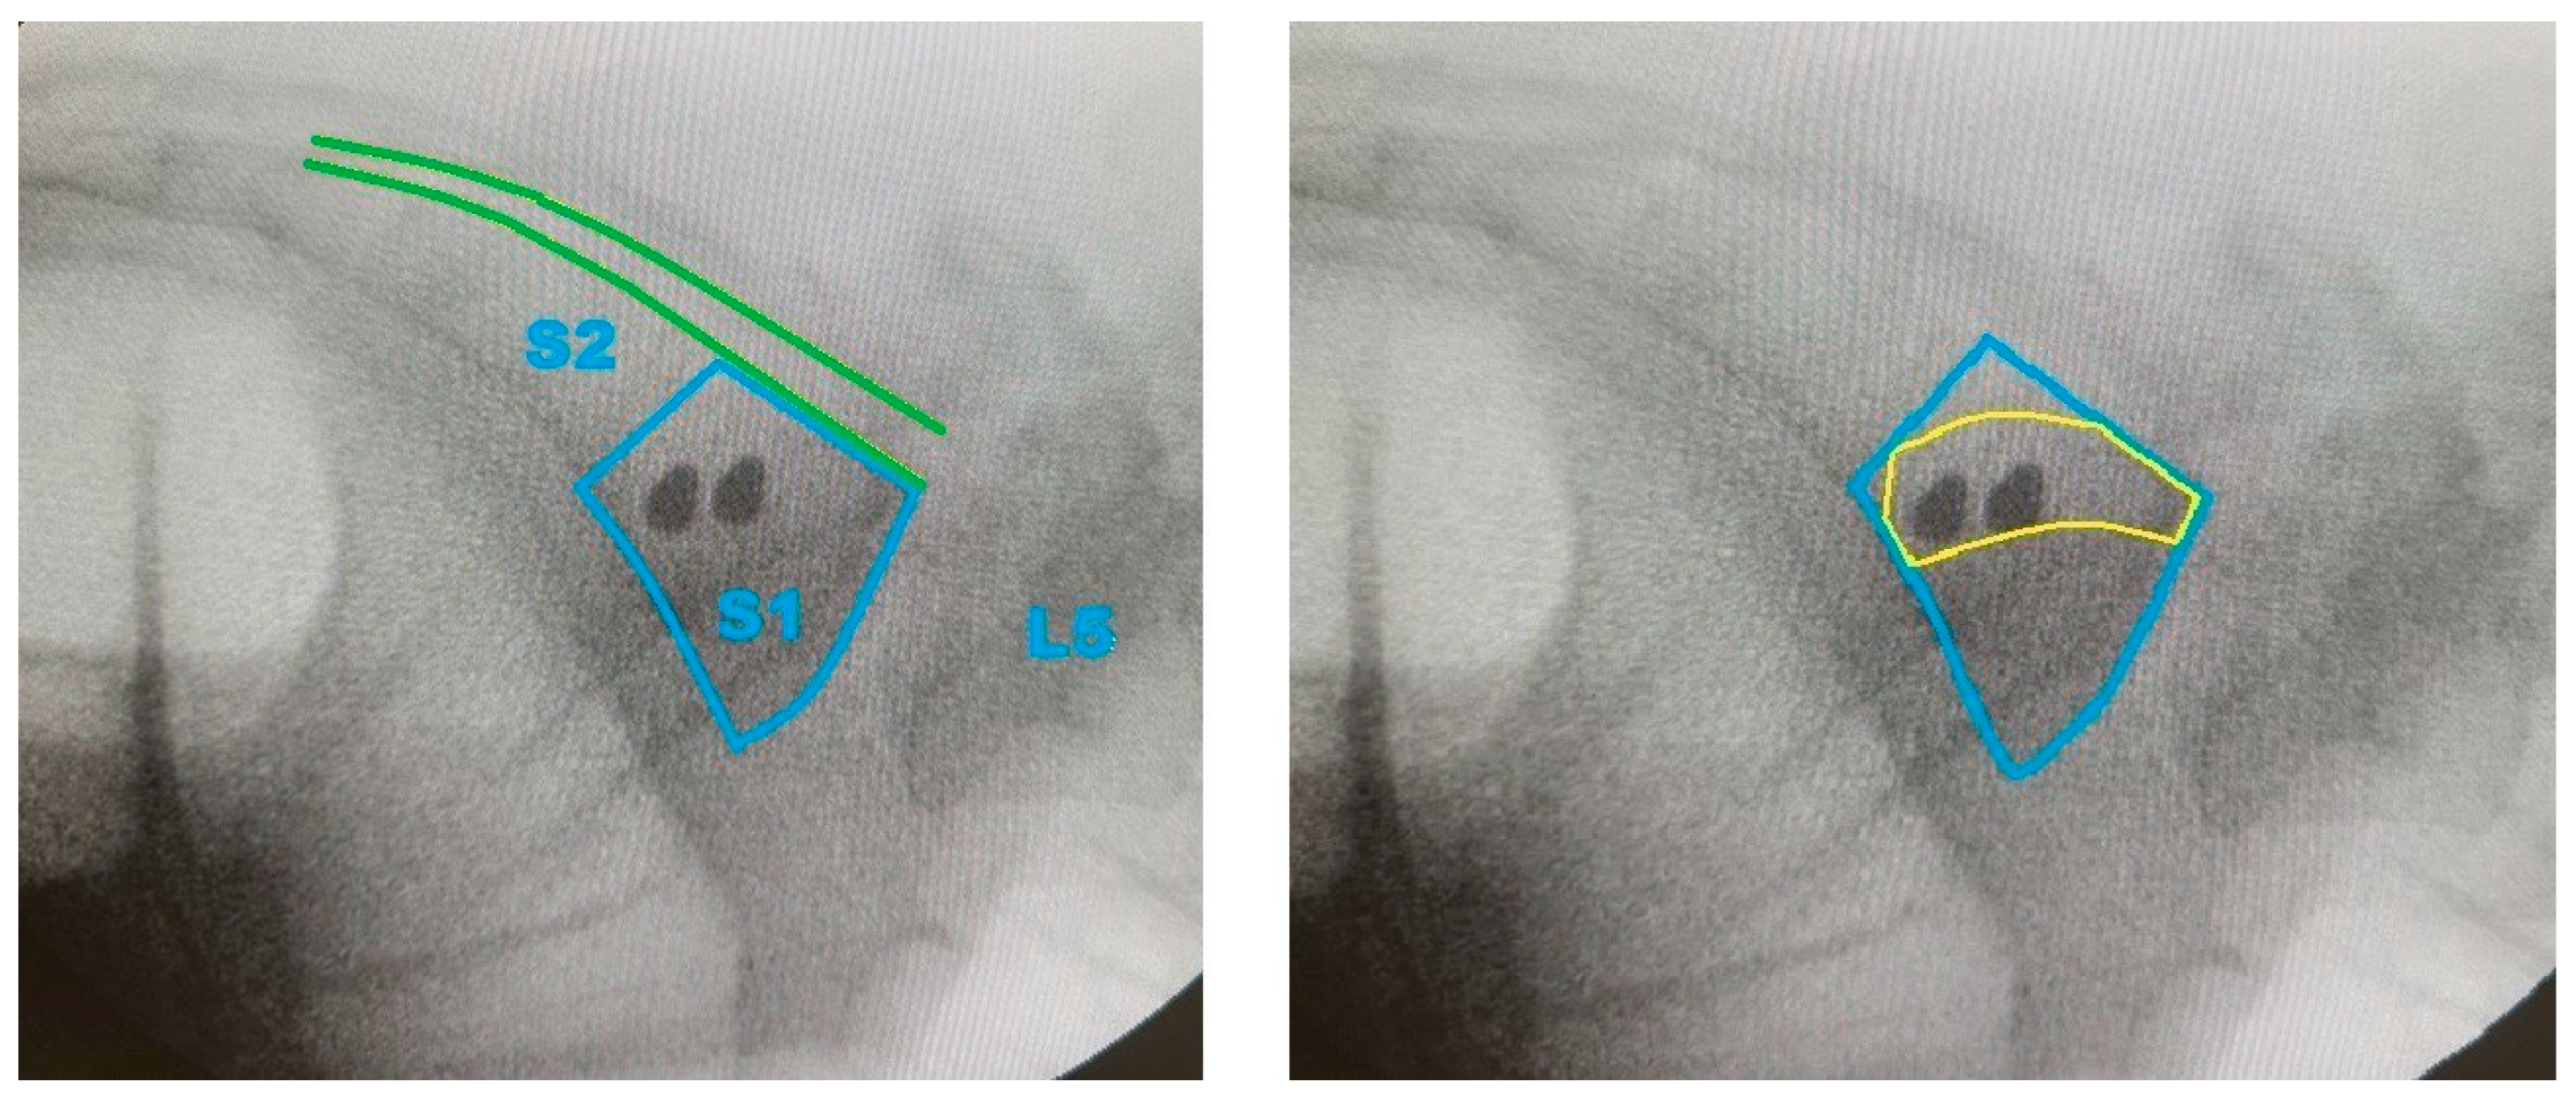

- Generation of Screw Trajectory Target Zone: Using the 2D projection, a patient-specific safe zone for screw placement was identified through a reproducible computational technique developed in this study. The resulting zone is referred to as the Ramadanov–Zabler Safe Zone for reference purposes. Regions with higher bone density were targeted as they suggested a greater likelihood that the screw would remain strictly intraosseous, thereby reducing the risk of cortical breaches or screw misplacement. The target zone served as a guide for the ideal screw trajectory during percutaneous SI screw fixation.

3.3. Safe Zone Identification